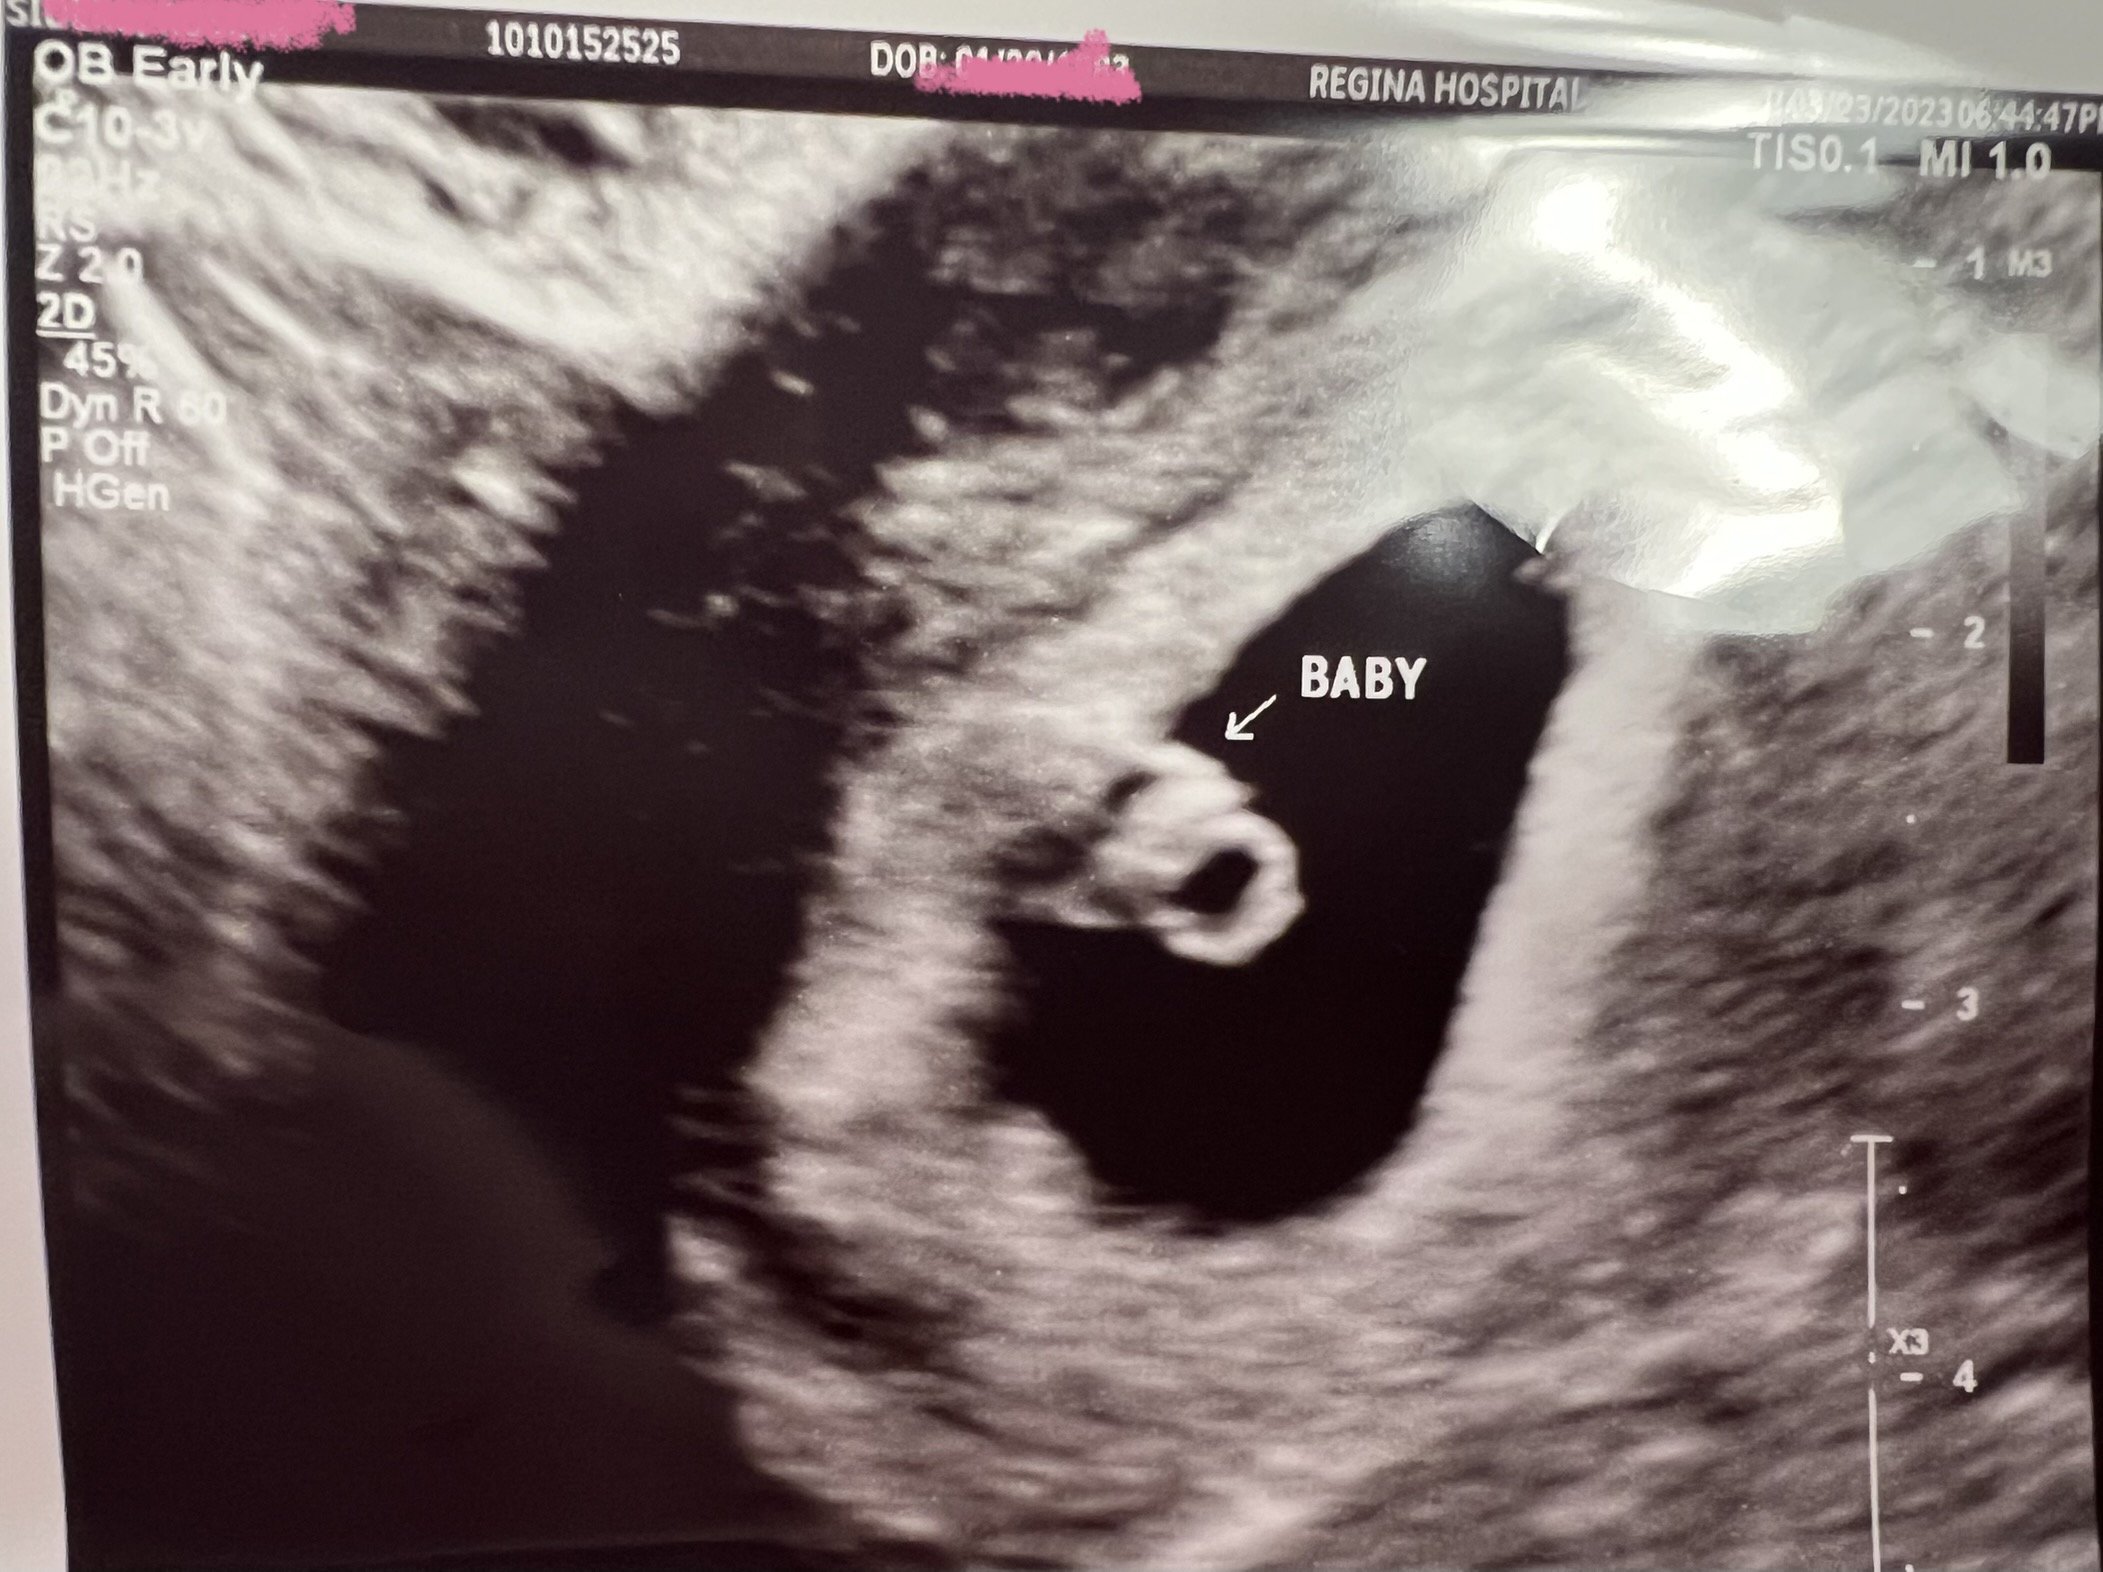

We had an early viability ultrasound due to previous complications. Not much to see at 5 weeks 2 days but everything that they should be able to see is there! Gestational sac and tiny little yolk sac. ❤️